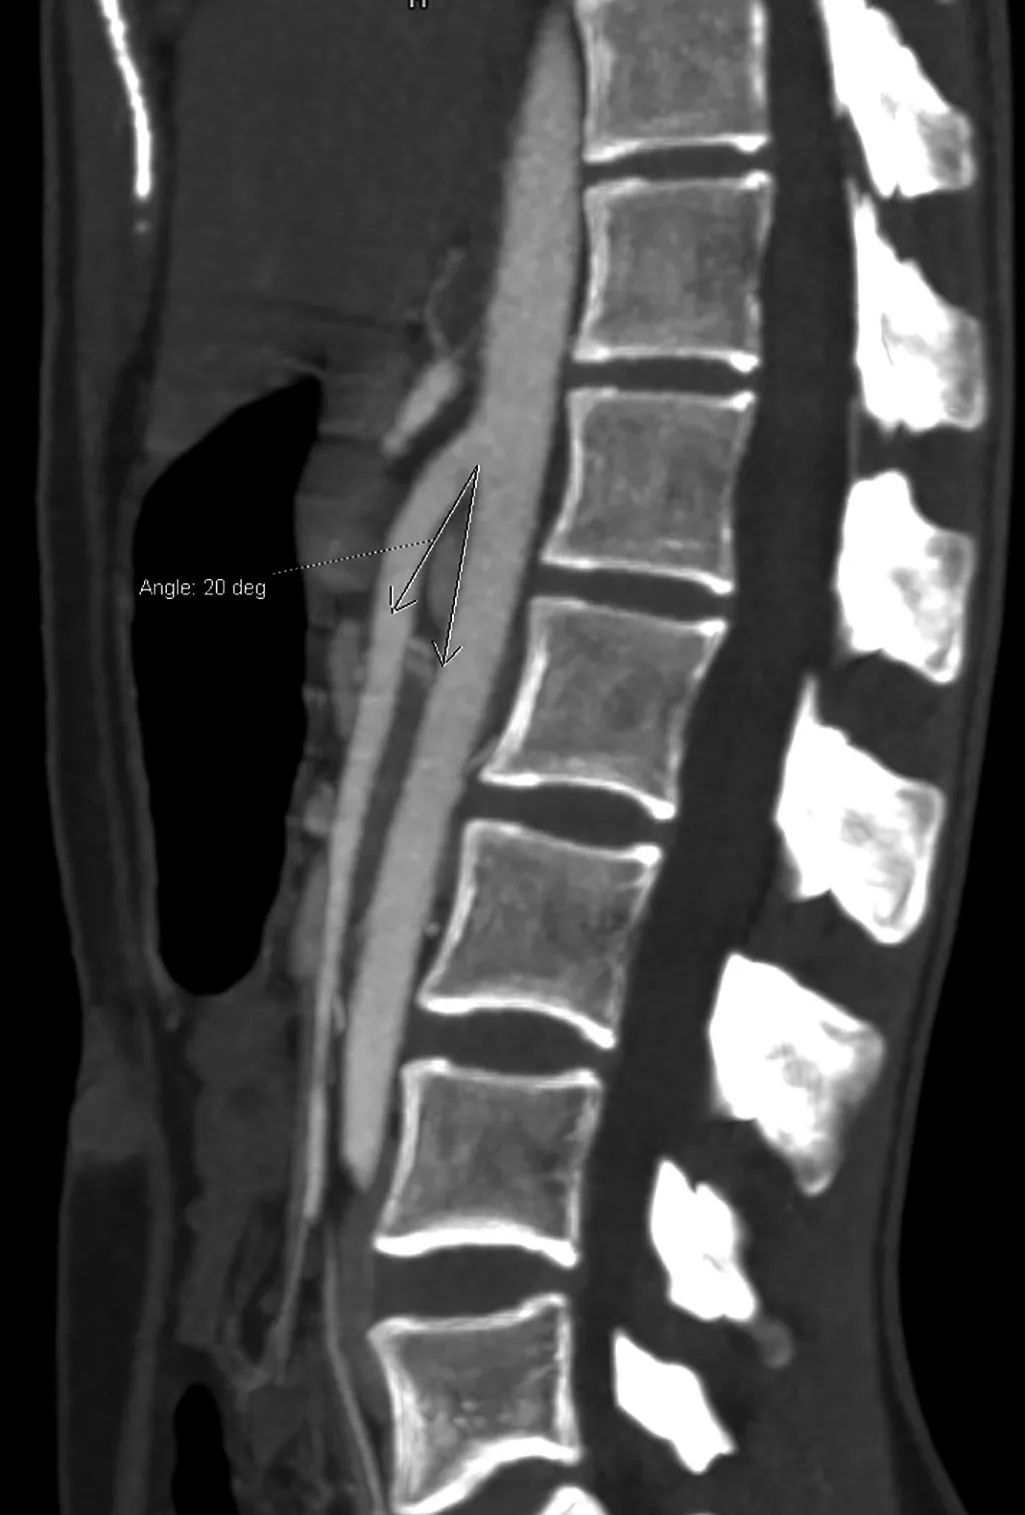

X 线钡餐常有十二指肠水平部脊柱中线处中断。主动脉和肠系膜上动脉之间的夹角20°。主动脉与肠系膜上动脉之间的距离2.9mm。

●主动脉和肠系膜上动脉之间的夹角≤25°是最敏感的诊断指标,特别是当主动脉与肠系膜上动脉之间的距离≤8mm时。